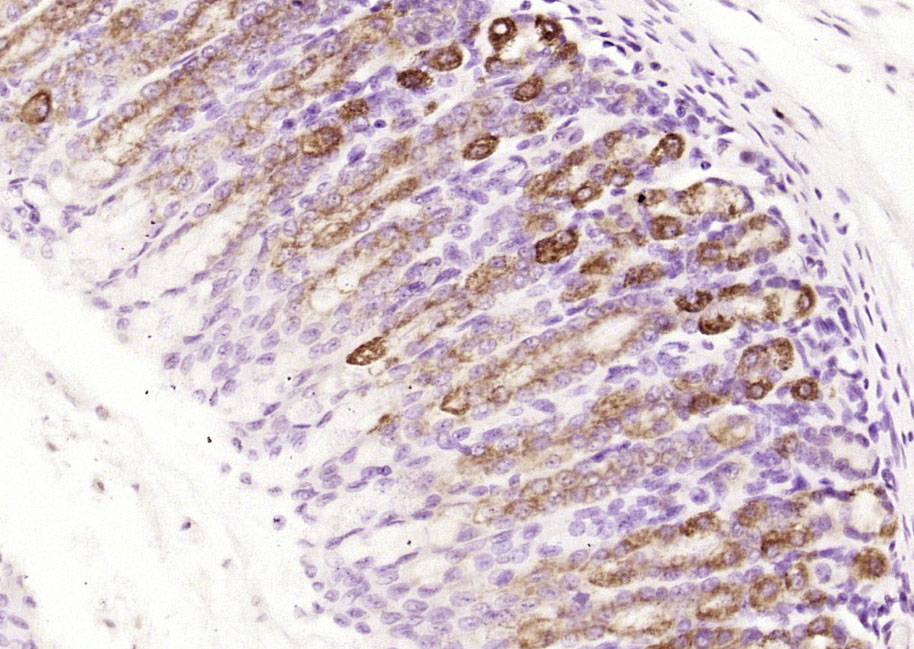

Paraformaldehyde-fixed, paraffin embedded (rat stomach); Antigen retrieval by boiling in sodium citrate buffer (pH6.0) for 15min; Block endogenous peroxidase by 3% hydrogen peroxide for 20 minutes; Blocking buffer (normal goat serum) at 37°C for 30min; Antibody incubation with (MUC5AC) Polyclonal Antibody, Unconjugated (bs-7166R) at 1:200 overnight at 4°C, followed by operating according to SP Kit(Rabbit) (sp-0023) instructionsand DAB staining.